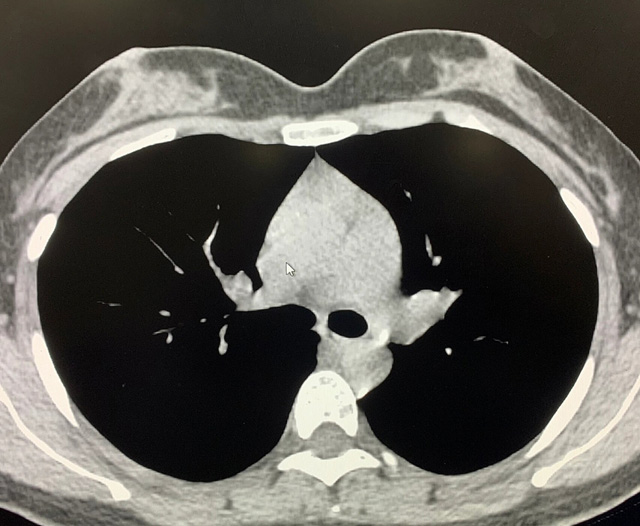

能譜純化技術的核心是通過物理濾過(如錫濾片)或軟件算法,選擇性濾除低能X射線光子,保留高能光子。在胸部低劑量CT掃描中顯著提升了圖像質量與輻射劑量的平衡。

優勢輻射劑量顯著降低相較于常規CT,輻射劑量減少約70%-90%,尤其適合需多次隨訪的高危人群(如肺癌篩查),降低輻射相關癌癥風險早期肺癌篩查效果明確可清晰檢測毫米級肺結節,顯著提高早期肺癌檢出率,降低死亡率。檢查快捷且普及性高單次掃描僅需數秒,無需對比劑,設備廣泛配置于基層醫院,便于大規模篩查。長期成本效益顯著雖單次費用與常規CT相近,但早期干預可大幅降低晚期治療費用及社會醫療負擔。技術優化提升圖像質量迭代重建算法(如ASIR、MBIR)在降低劑量同時減少噪聲,平衡影像質量與安全性。